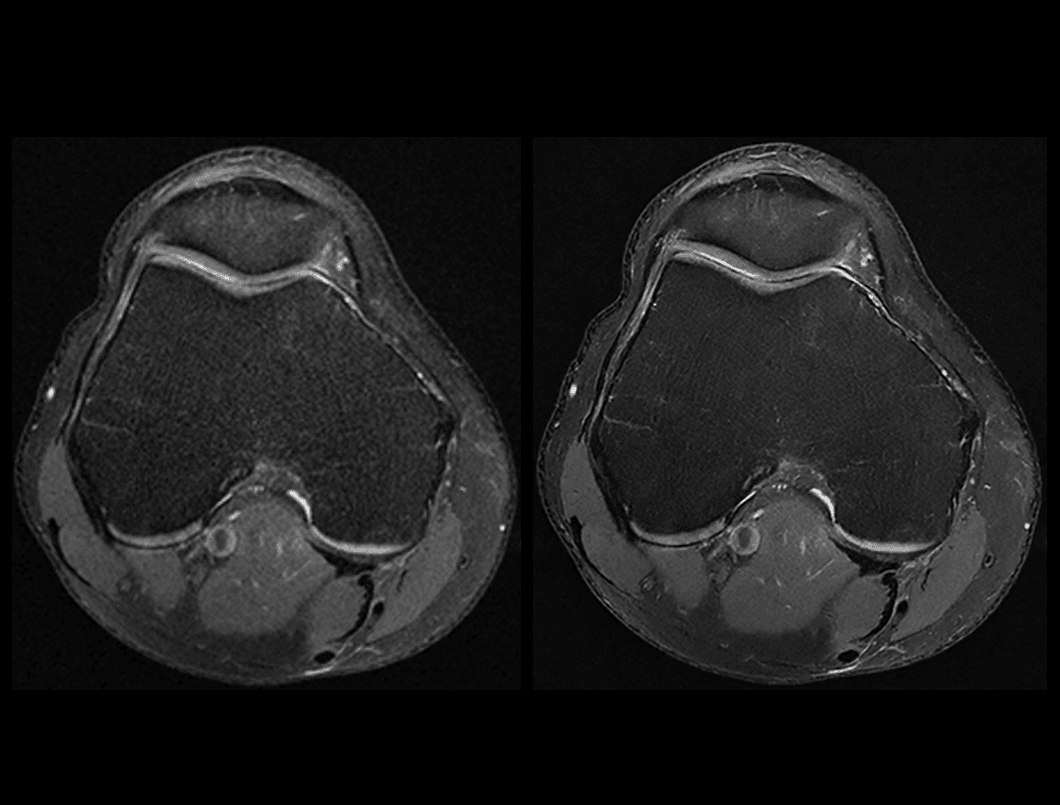

Genunchi PDW FS

Comparație între tehnica convențională (2:32 min) și uAIFI DeepRecon™ (2:32 min), cu rezoluție de 0,35 × 0,35 × 3 mm³, evidențiind claritatea îmbunătățită și detaliile superioare obținute prin reconstrucția AI.